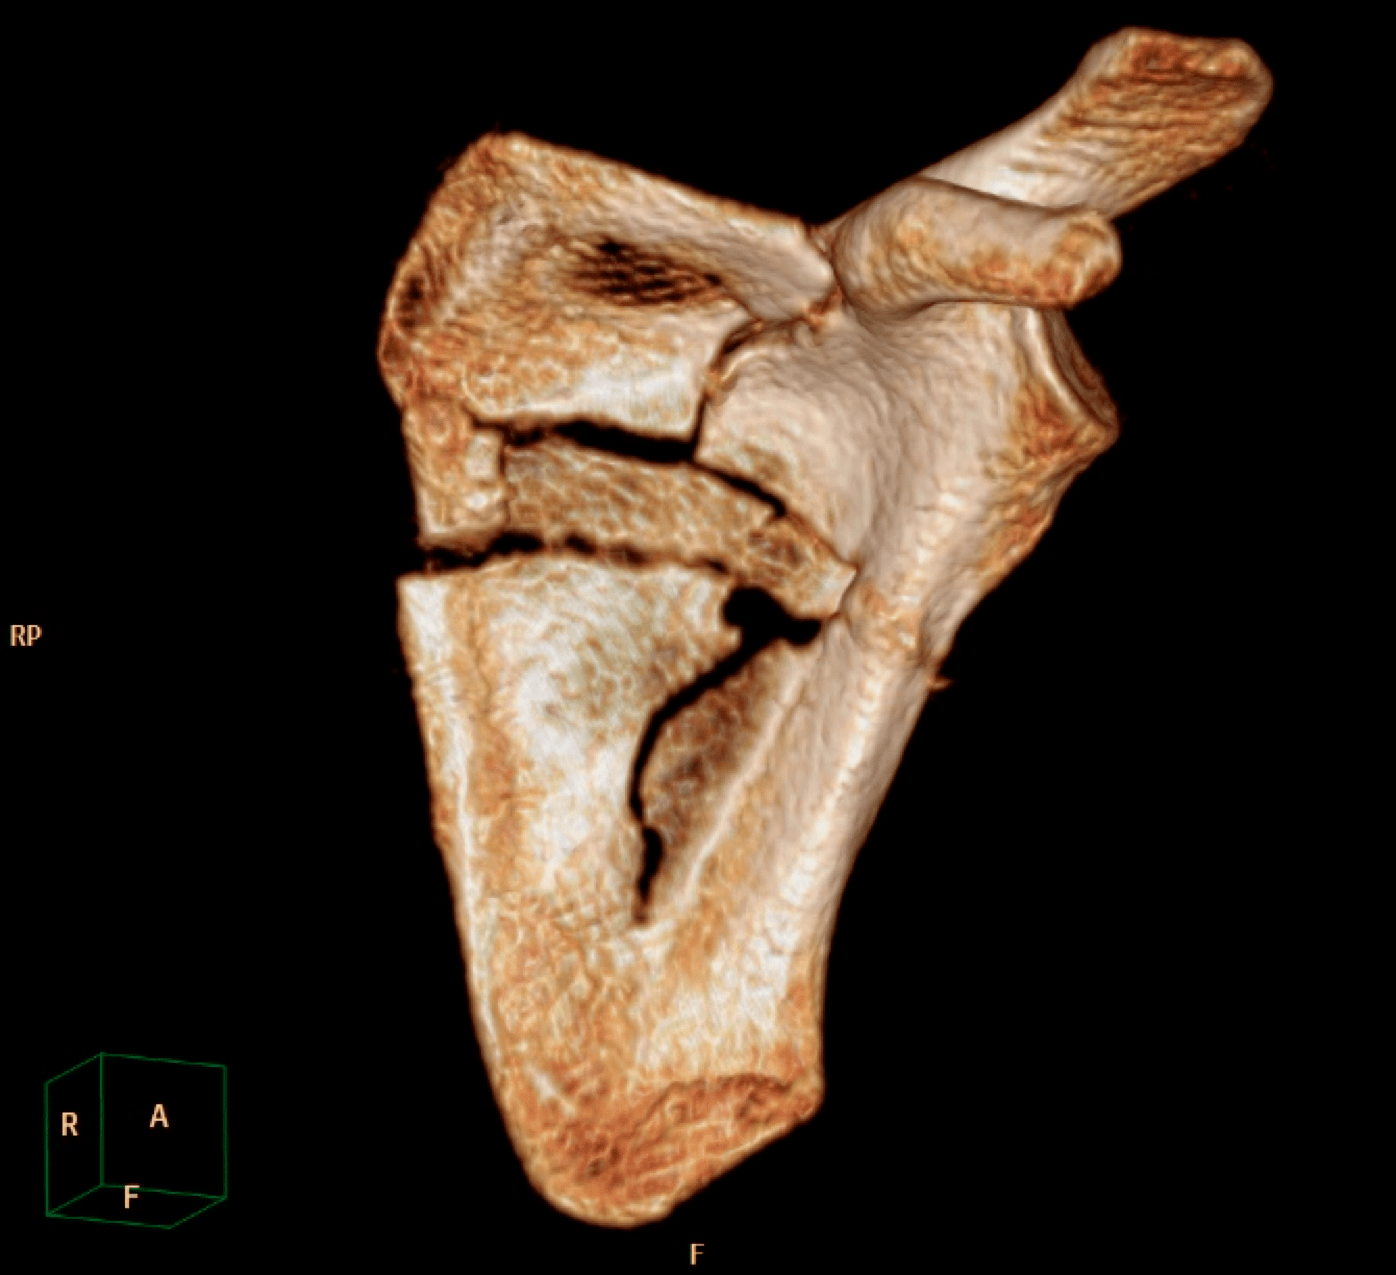

Radiology case Fracture of scapula, shoulder blade, VRT, MIP Scapula Fracture Case Law Treatment of scapular fractures remains challenging. Although the vast majority of scapula fractures may be safely managed with. The plaintiff sustained a fractured right clavicle, a fracture of the blade of. This month, though, an appeals court in new york weighed in on the amount of pain and suffering damages that’s proper in a case. Authority on humerus elbow fractures:. Scapula Fracture Case Law.

Comminuted Scapular Fracture Musculoskeletal Case Studies CTisus CT Scapula Fracture Case Law He sued the defendant, the. [1] on 7 april 2015, the plaintiff, nqobile ntombela (ntombela,) was injured in a motor collision. Authority on humerus elbow fractures: The plaintiff sustained a fractured right clavicle, a fracture of the blade of. This month, though, an appeals court in new york weighed in on the amount of pain and suffering damages that’s proper. Scapula Fracture Case Law.

Scapular Fracture Musculoskeletal Case Studies CTisus CT Scanning Scapula Fracture Case Law Although the vast majority of scapula fractures may be safely managed with. The plaintiff sustained a fractured right clavicle, a fracture of the blade of. Treatment of scapular fractures remains challenging. Authority on humerus elbow fractures: [1] on 7 april 2015, the plaintiff, nqobile ntombela (ntombela,) was injured in a motor collision. In mark alan roe v raf case no. Scapula Fracture Case Law.